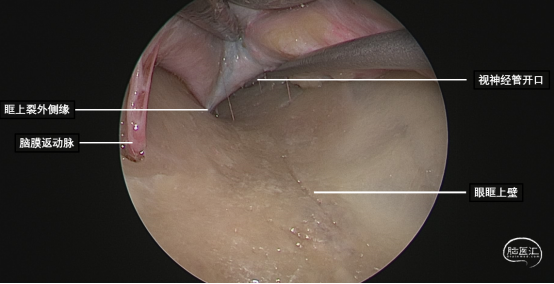

研究表明此入路除细小的滋养血管外无其他重要结构!皮肤切口选择近眶缘眉弓美容切口,紧贴眶上壁分离骨膜,保护眶筋膜,病变紧贴眶上壁,导航下确定眶尖紧贴眶上壁的病变,外观呈浅紫兰色,考虑既往有出血所致,显露肿瘤!

磨除局部少许隆起的骨嵴以增加操作空间,切开眶骨膜分离并完整切除病变,术中证实为海绵状血管瘤,直径约1厘米,手术全程在内镜下完成。

球后眶尖部位及海绵窦区的病变因为位置深在,周围重要结构众多,对神经外科医生具有极高的挑战性。神经内镜技术发展给我们提供了一条思路。我们通过相关解剖研究发现,病变位于海绵窦外侧壁、颈内动脉外侧、颞极内侧,可选择经眶外侧壁入路;病变位于眶尖内侧,累及海绵窦侧壁,经眶内侧壁入路更为适合;病变主体位于鞍区向一侧海绵窦侧壁侵袭,可以考虑内镜经鼻入路。眶内上壁病变,因为无重要结构,经眶入路最适合!